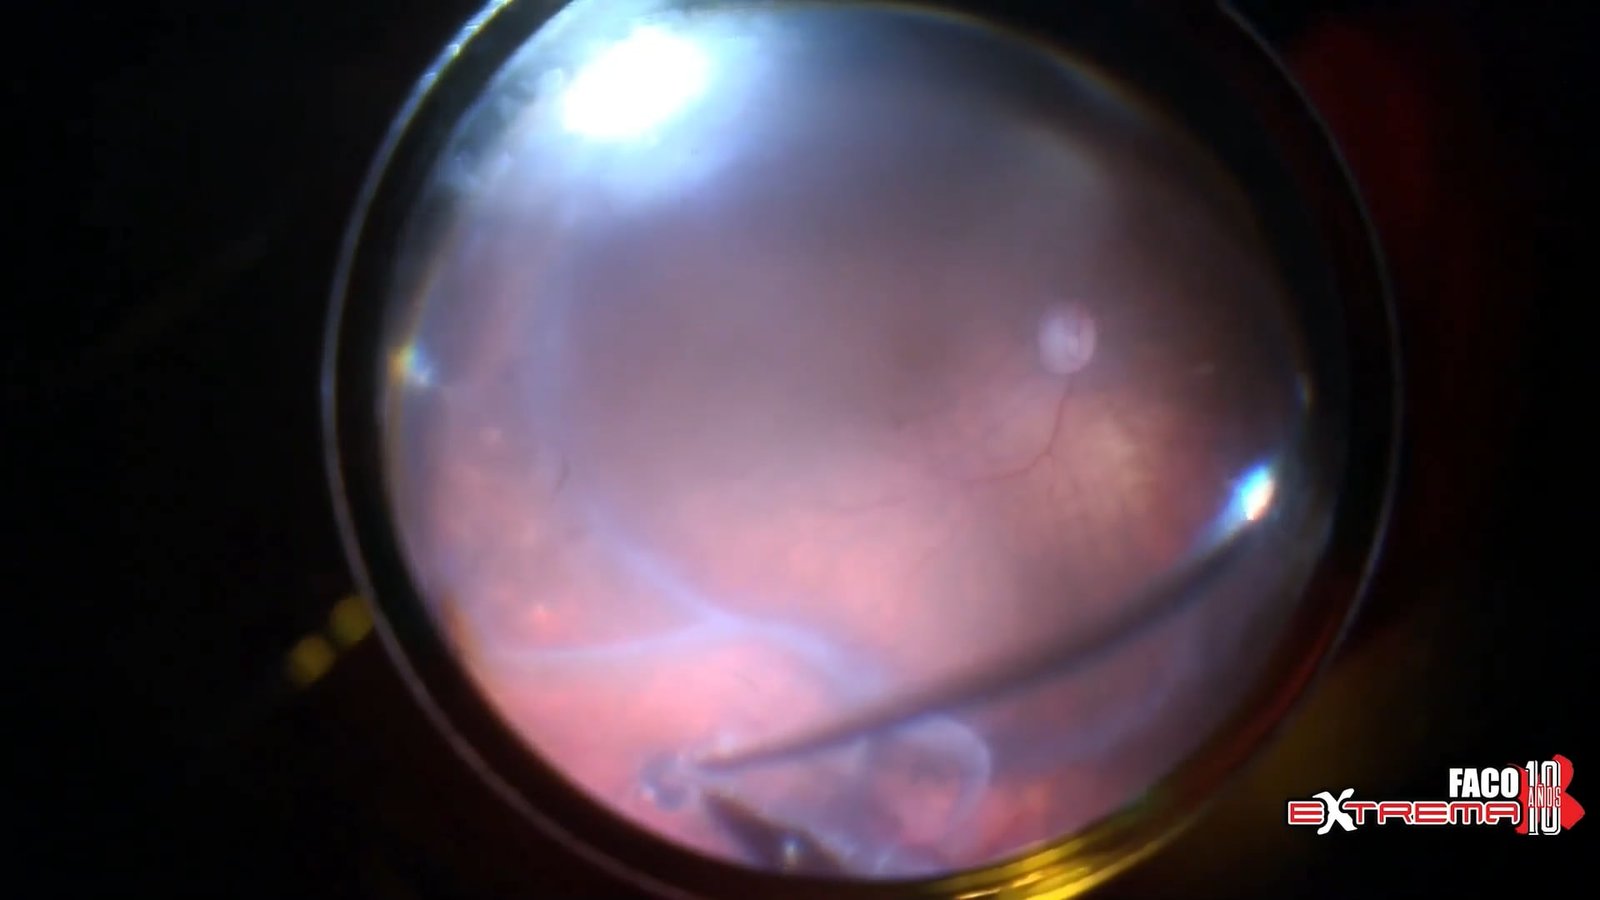

Contusión retinal, coroidea y CEIO